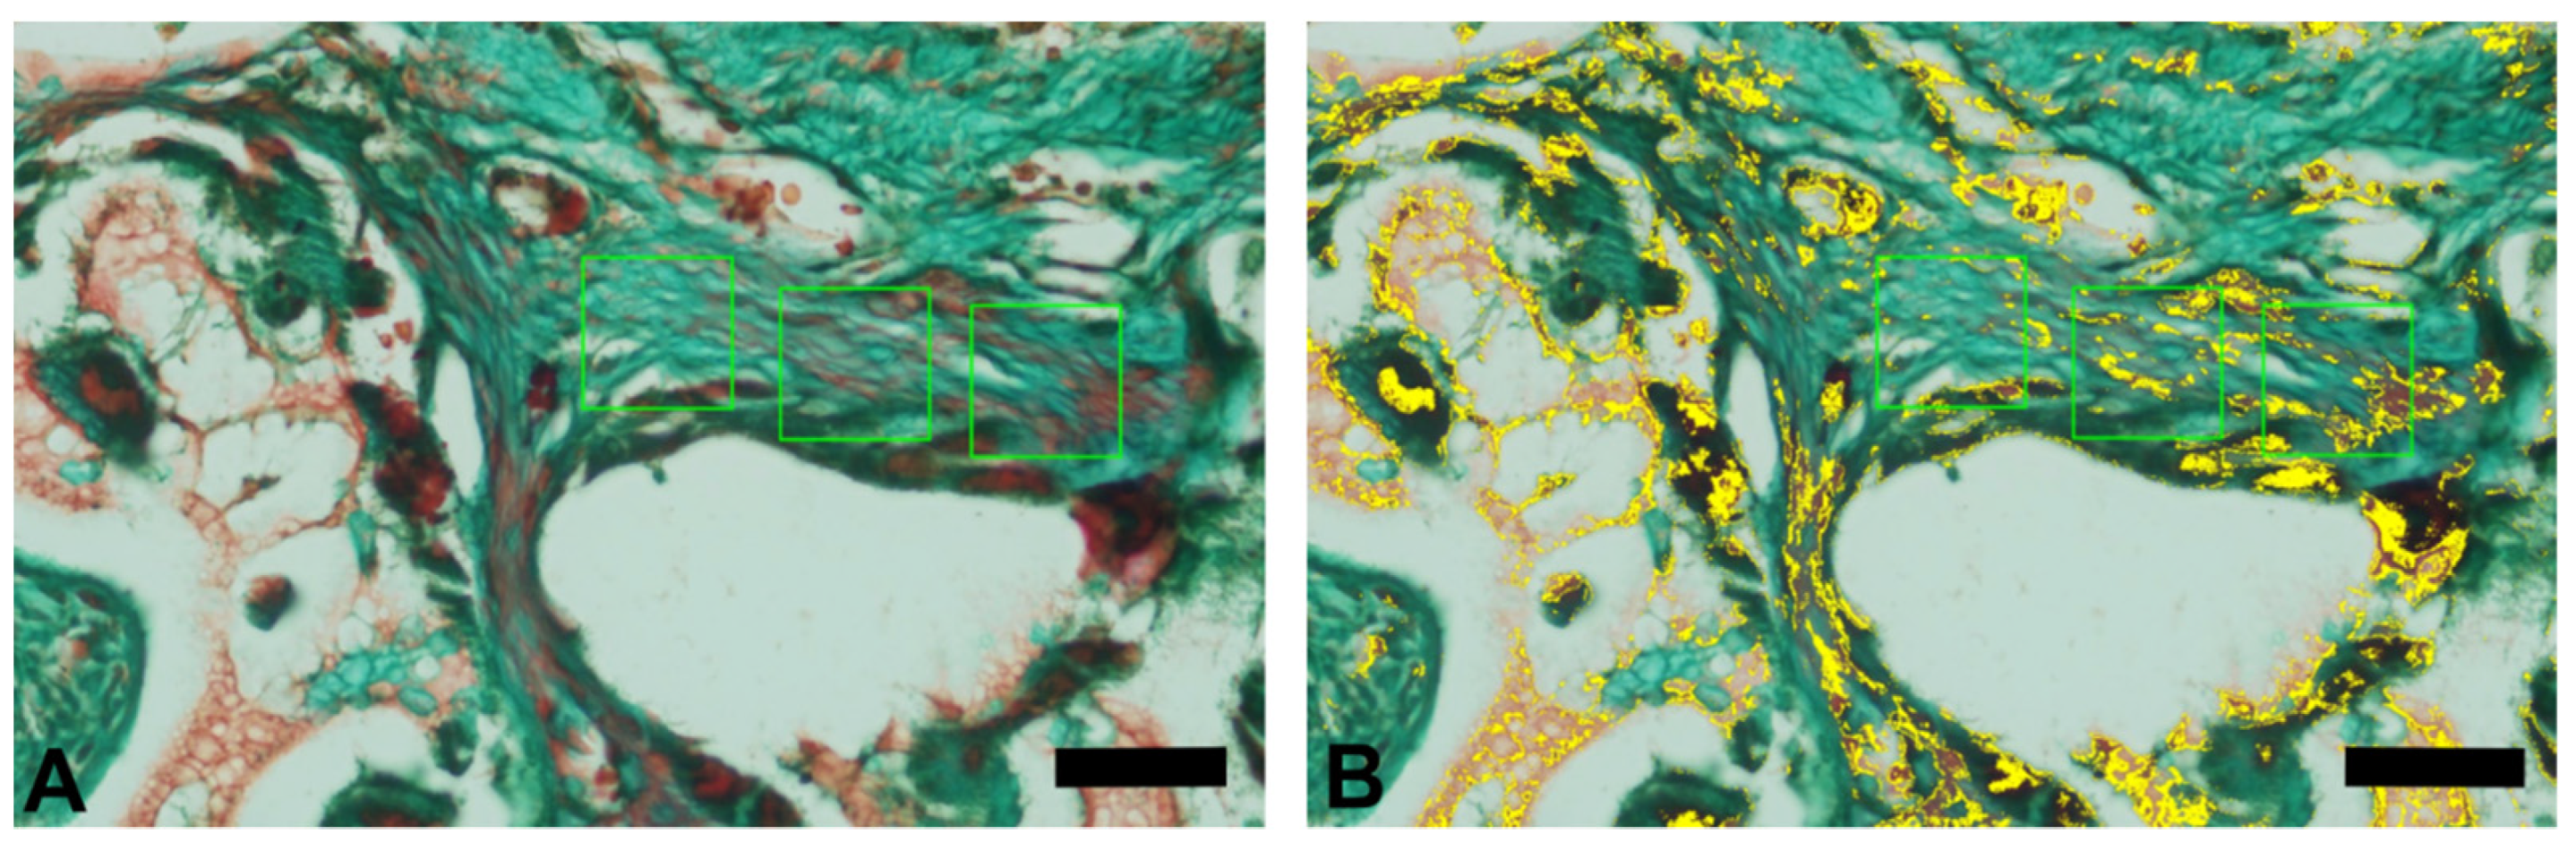

3.1. Goldner’s Trichromic Staining